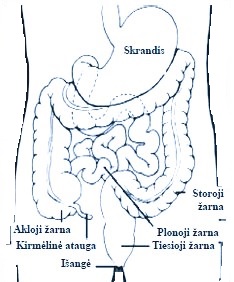

Storosios žarnos vėžys

Kolorektalinis vėžys ar „storosios žarnos” vėžys yra viena iš 5 dažniausiai pasitaikančių vėžio lokalizacijų Lietuvoje. Lietuvoje kasmet užregistruojama apie 1400 naujų šios ligos atvejų, per metus nuo jos miršta daugiau, kaip 800 žmonių.